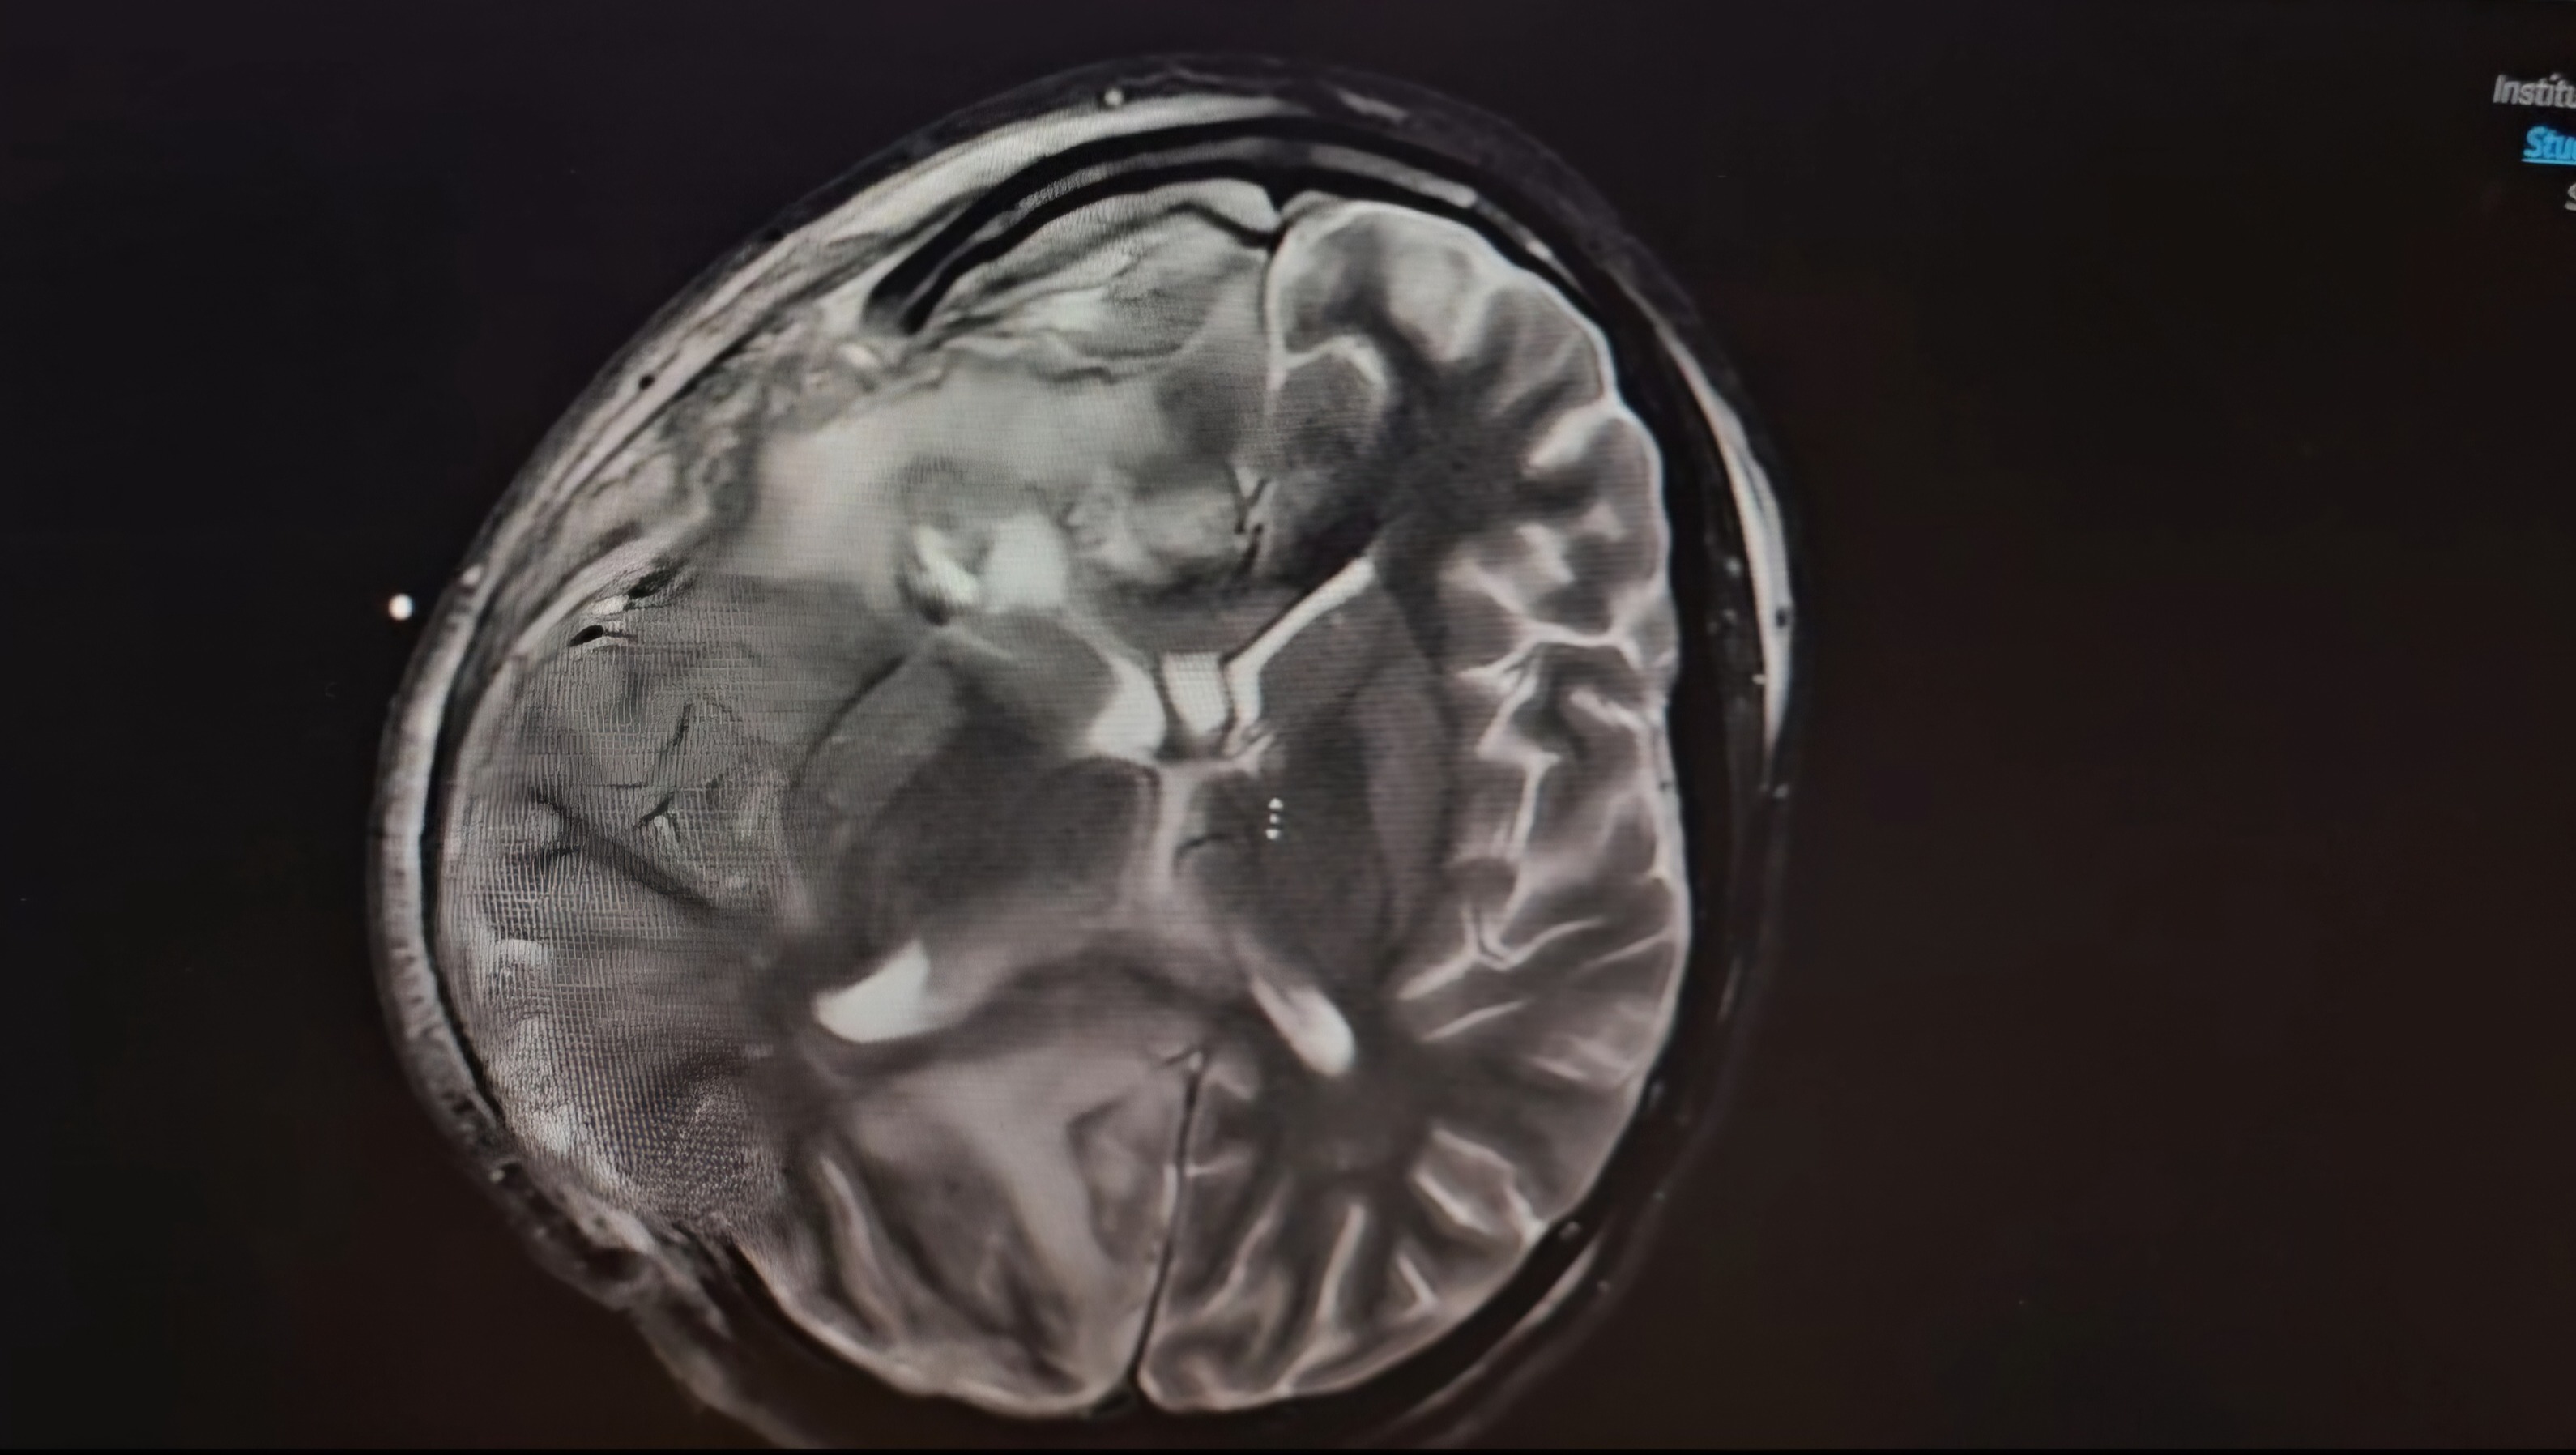

It all began with what seemed like a routine sinus infection, but quickly escalated to a life-threatening condition. The infection spread to the right side of her brain, causing serious complications. Alejandra is now nonverbal and unable to move the left side of her body, requiring multiple surgeries and ongoing medical care.

Her condition has been a constant rollercoaster of ups and downs, with moments of hope followed by heartbreaking setbacks. The infection has been diagnosed as a brain abscess, linked to Streptococcus intermedius—a rare and dangerous bacteria that has left her in a fragile state. The medical team is doing everything they can, but Alejandra’s prognosis remains uncertain, and her recovery journey will be long and difficult.

Alejandra’s case is part of a worrying trend. The infection that led to her brain abscess started as a sinus issue, and doctors are noticing more children developing similar infections that spread to the brain. Just last year, Dr. Taryn Bragg, Alejandra's surgeon, worked with the CDC to investigate a rise in brain abscess cases in children. These abscesses often follow common illnesses like sinus infections or earaches, but in some cases, they rapidly escalate to more serious conditions that require multiple surgeries.